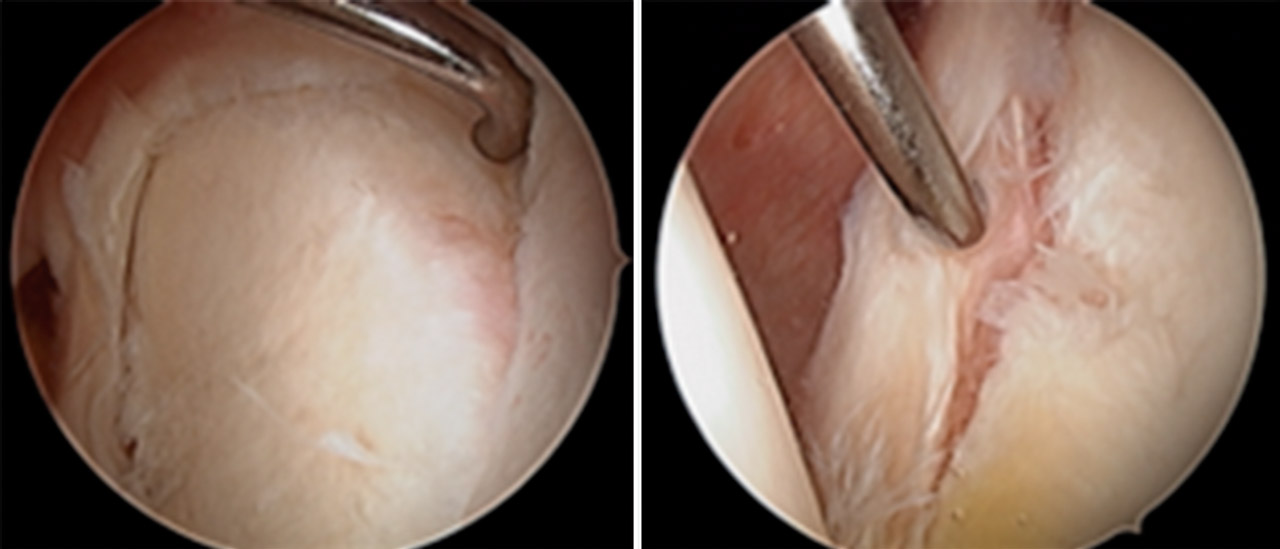

A la exploración física se evidenció movilidad completa, maniobras negativas para lesión de manguito de rotador o patología de articulación acromioclavicular. La exploración física fue positiva y compatible con lesión de SLAP (superior labrum anterior to posterior), confirmada con la artrorresonancia magnética (artro-RM) y diagnosticada como SLAP de tipo II; se programó para reparación artroscópica (Figura 1).

Se inició la artroscopia mediante el portal A habitual (Figura 3) y a través del portal E se confirmó la lesión de SLAP de tipo II con el gancho palpador (Figura 4). Confirmamos la laceración de la porción intraarticular del músculo bíceps braquial (Figura 5). Se realizó el portal D de trabajo para insertar un anclaje y comenzar a realizar la tenodesis de la porción larga del músculo bíceps braquial (PLB). En ese momento, el paciente presentó una grave inestabilidad hemodinámica que obligó a su colocación en decúbito supino y a despertarlo de la anestesia general. En esa posición, se decidió efectuar una tenotomía de la PLB para salvar el procedimiento (Figura 5).